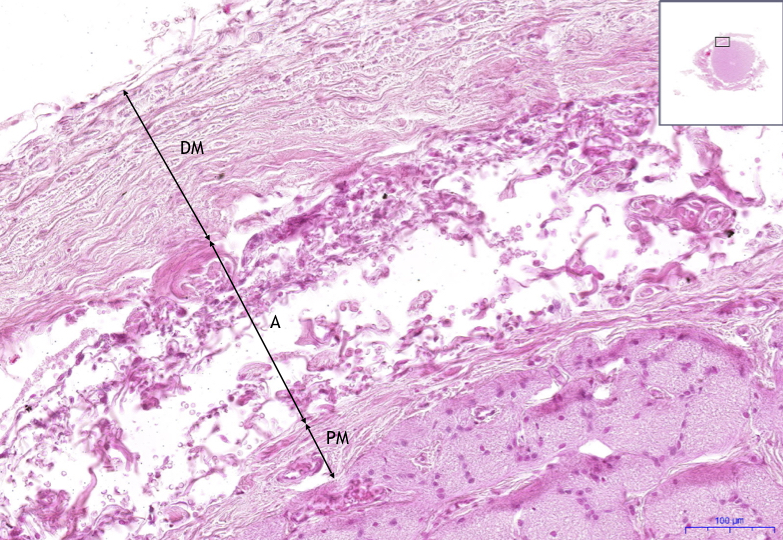

Optic nerve – HE, 11.7x

- 1) PM – pia mater

- 2) DM – dura mater